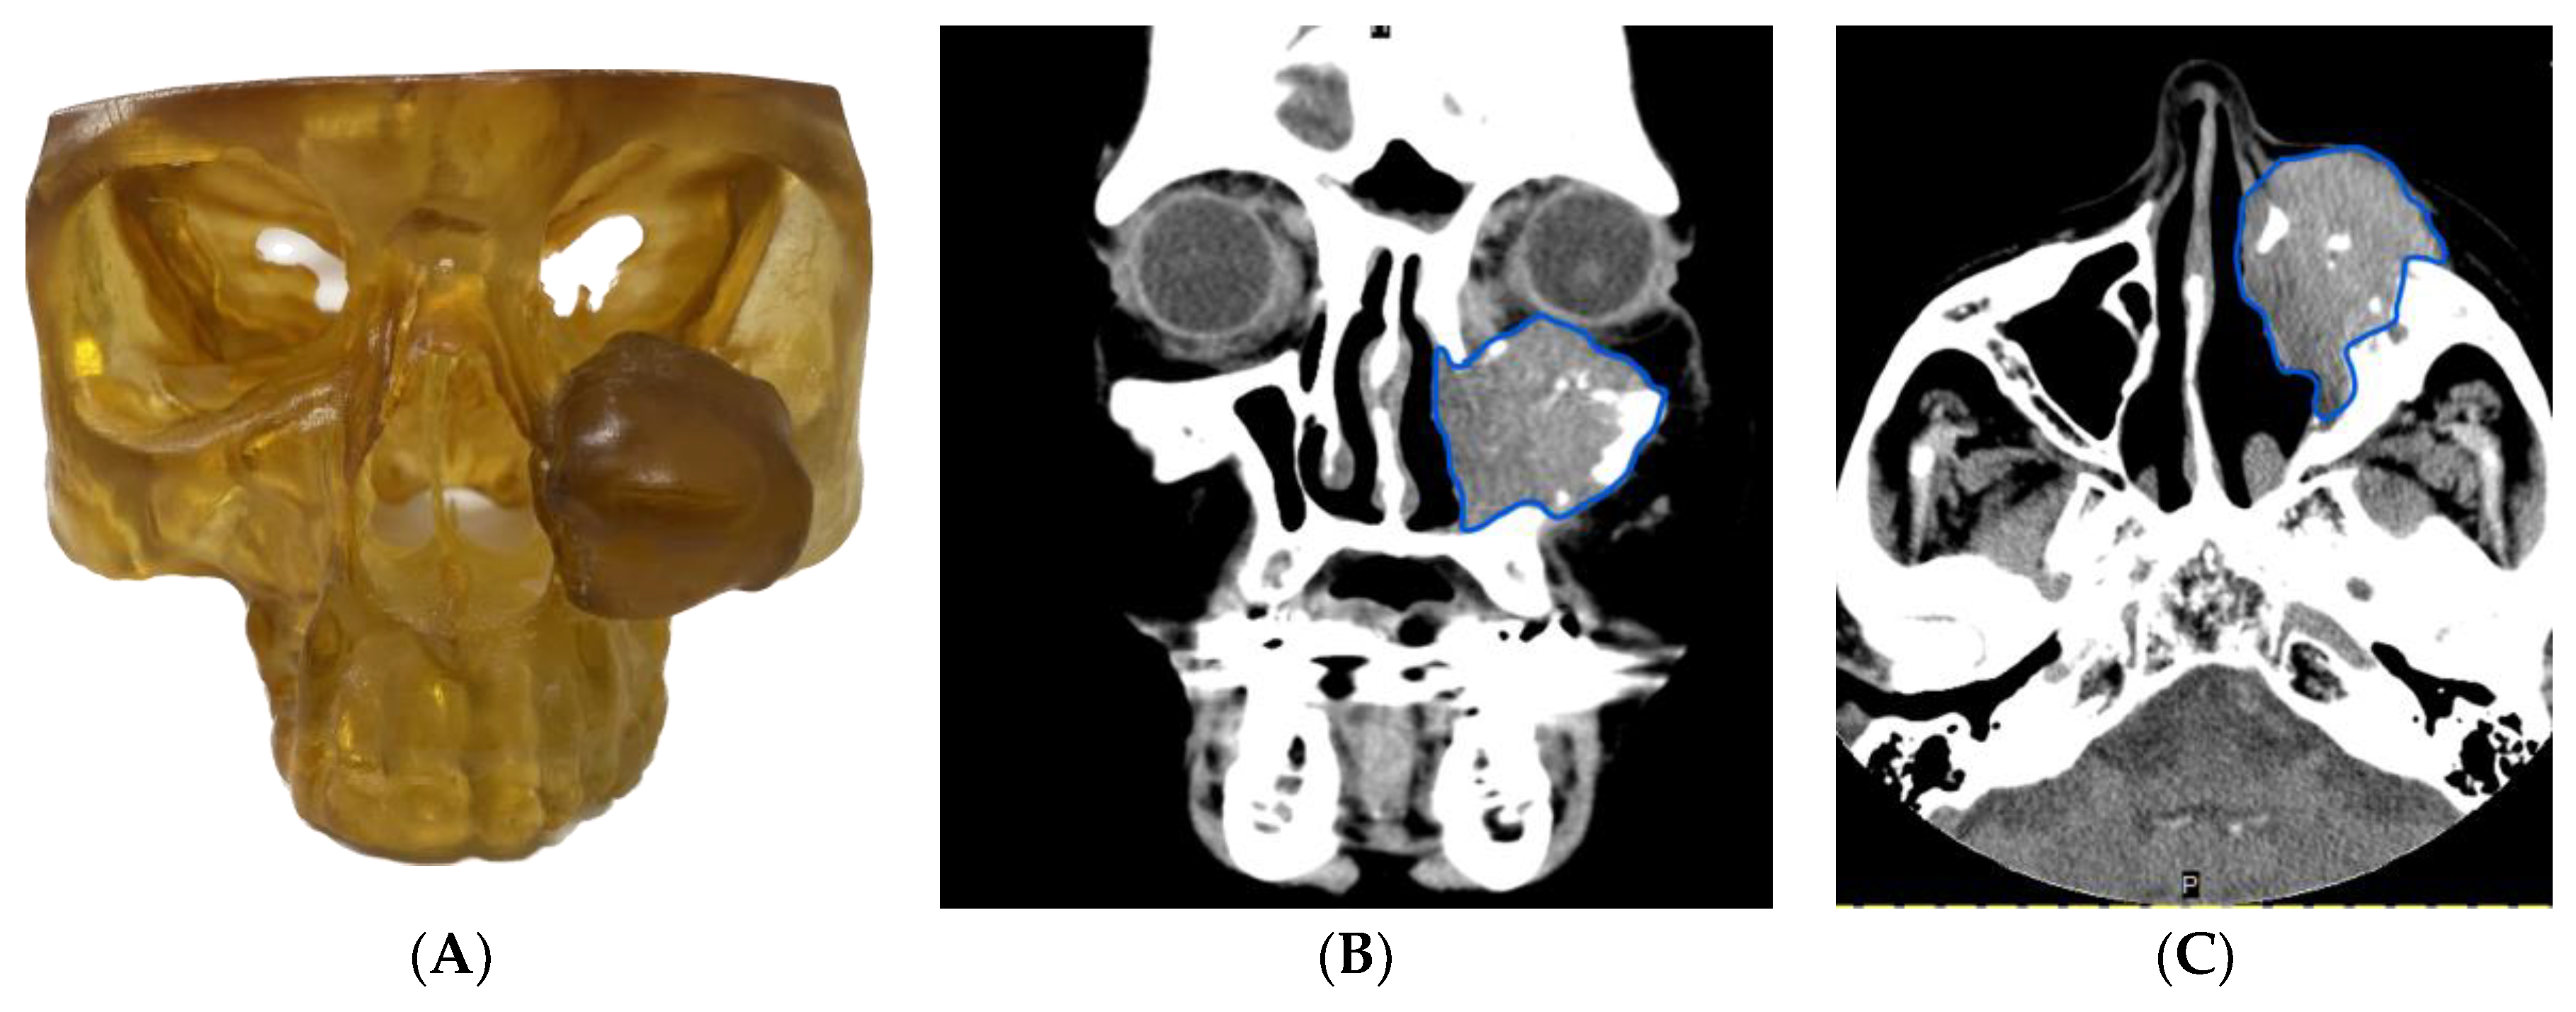

3.1.3. Case 3: Use of Virtual Surgical Planning and a 3D Model in Resident and Fellow Education